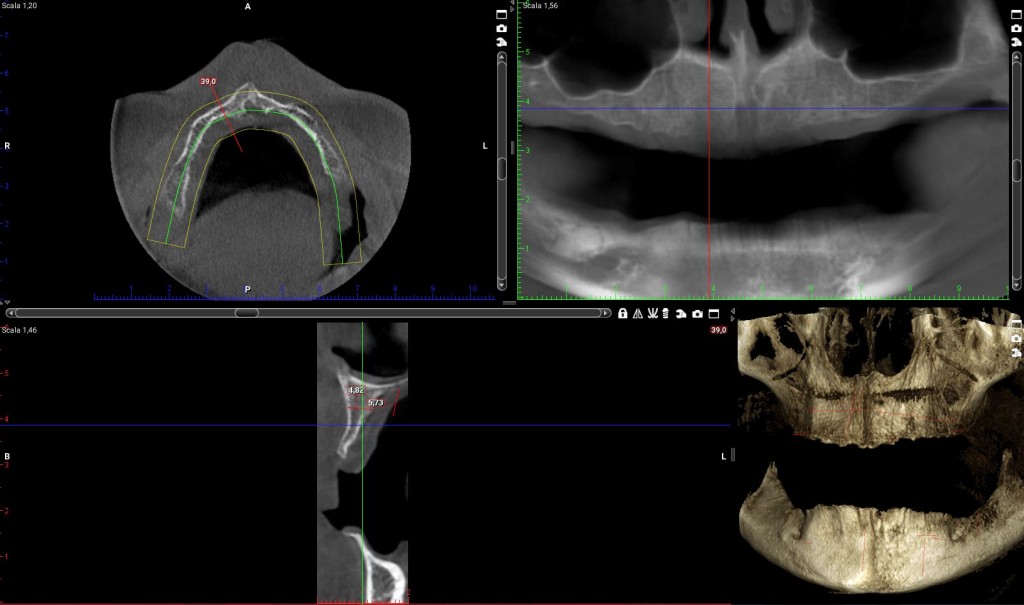

Impianto distale di destra:la cresta è larga molto meno di 4mm per tutta la sua estensione in altezza. E di lì l’impianto ci deve passare!

il programma di progettazione, che tra l’altro fornisce una bella area di sicurezza intorno al volume della fixture, dice “NON SI PUO”!

Impianto mesiale di destra:

se vogliamo ricercare uno spessore di cresta che superi i 4 mm dobbiamo andare a 5mm dal pavimento del naso. Io non farei un carico immediato full-arch su un impianto da 5mm!

Anche qui il programma di simulazione dice “NON SI PUO’”!